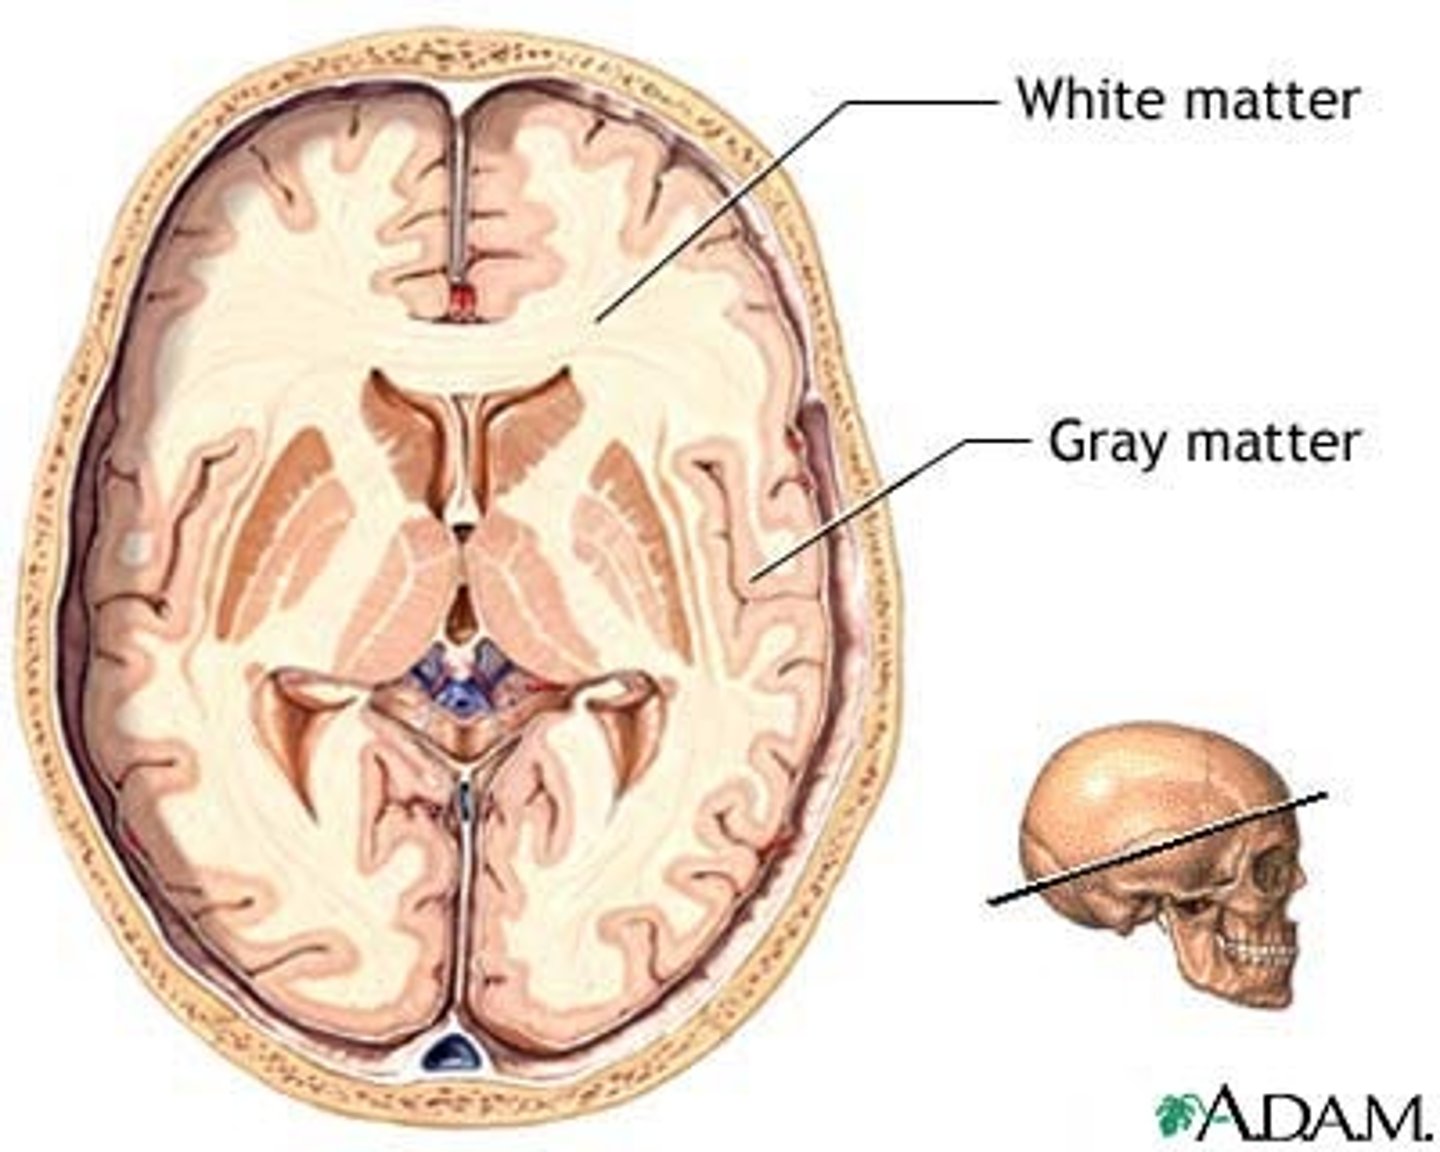

Layers of the Cerebrum

Cerebral Cortex (gray matter),

Cerebral Medulla (white matter),

Basal Nuclei

Cerebral Cortex

Gray matter,

Outer layer of cortex about 2-4mm thick and accounts for 40% of total brain mass,

Composed mostly of interneuronal cell bodies,

Highly convoluted,

Involved in higher brain functions (speech, memory, logic, etc.)

Cerebral Medulla

White matter,

Myelinated nerve tracts inside the gray matter that are responsible for communication between cerebral areas and between cerebral cortex and lower CNS centers,

Corpus callosum

Corpus Callosum

Dense band of myelinated nerve tracts that allow communication between left and right cerebral hemispheres

Basal Nuclei

Internal islands of gray matter dispersed bilaterally in the inferior cerebrum, diencephalon, and midbrain,

Not noted as distinct anatomical structures but functional areas,

Important in controlling and modifying motor functions